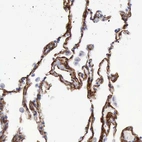

Immunohistochemistry analysis in human lung and skeletal muscle tissues using HPA000980 antibody. Corresponding AOC3 RNA-seq data are presented for the same tissues.